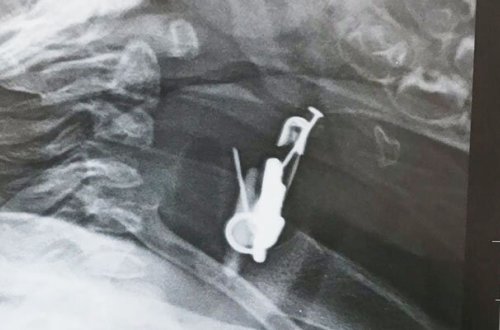

Gözdəyməmək üçün vurmuşdular, körpə uddu

- Azərbaycanda+Foto

körpənin

altı

uşağın

çıxarılıb

mədəsindən

digər

aylıq

sancağı

üzərində

saylı

körpə

qarayev

adına

əşyaları

mədəsində

xəstəxanaya

bakıya